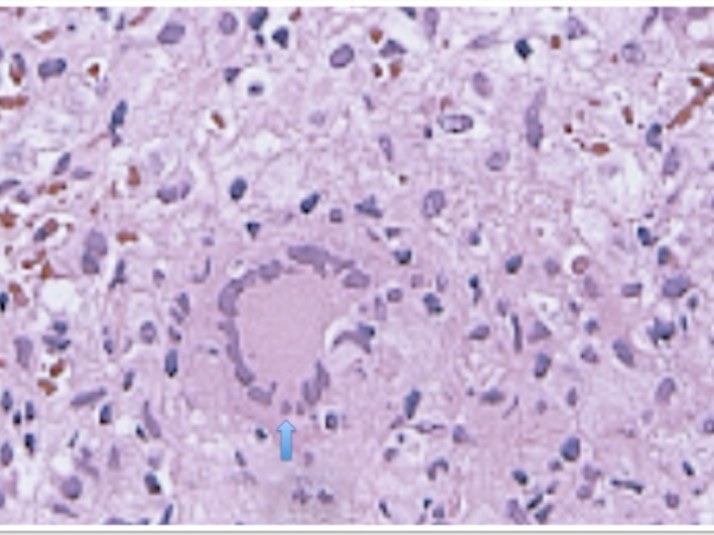

Laboratory analysis showed hemoglobin, 10.9 g/dL; white blood cell count, 9,800 cells/mm3, serum albumin, serum total bilirubin, alanine aminotransferase, aspartate aminotransferase, prothrombin time, hepatitis B surface antigen, and antibodies to hepatitis C, serum alpha-fetoprotein (AFP), carcinoembryonic antigen and carbohydrate antigen 19-9 (CA 19-9) were within normal range. Blood cultures were negative. Chest x-ray was normal. Ultrasound of abdomen showed a 10 cm hypoechogenic lesion in left liver (Figure 1). An abdominal CT showed a well-defined heterogeneous mass situated in his left hepatic lobe measuring 10 cm × 7 cm (Figure 2, Figure 3). The lesion featured central necrosis, a hyper-dense rim and a mild enrichment from the arterial phase in the CT, The diagnosis of primary hepatic tumor was suspected. An ultrasonography-guided needle biopsy of the liver was scheduled in order to rule out malignancy and to have a complete diagnosis. Cytology demonstrated a tuberculosis granuloma, acid-fast bacilli culture was positive (Figure 4). Anti-tuberculous therapy including isoniazid, rifampin, ethambutol, and pyrazinamide were prescribed. The patient completed the 6-month course of medication with success. The patient’s appetite and body weight were restored to previous levels. One year after the completion of treatment, the patient remained completely asymptomatic with disease free.

Figure 4.Hepatic histopathology of patient showing granuloma

CT-guided aspiration and biopsy can confirm the diagnosis. Percutaneous needle biopsy of the liver using ultrasound, CT has greater than 90 percent sensitivity. In case of pseudotumor tuberculosis mimicking a carcinoma, the role of biopsy is important because it can change therapeutic attitudes. The definitive diagnosis of this disease is conventionally made by histological analysis of caseating granuloma or demonstration of acid-fast bacilli on culture of biopsy specimen 13.